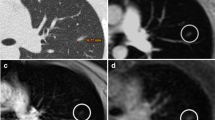

The qualitative assessment of cones and the fast spin-echo sequence revealed increased lung parenchymal intensity in young children depicted by cones that decreased with increasing age (Figs. 7, 8 and 9). The fast spin-echo sequence failed to show any contrast change depending on age.

Axial slices at carina level of a 5-month-old male control scanned with (a) cones and (b) fast spin echo. Cones provides higher contrast inside the lungs compared to the background and the signal of the trachea, which indicates capture of the lung parenchyma. Fast spin echo does not show any higher lung contrast. Qualitatively, cones delivers the highest lung contrast for newborns, compared to older patients (shown in Figs. 8 and 9)

Axial slices at the carina level of a 31-month-old girl control subject scanned with (a) cones and (b) fast spin-echo sequence. Cones provides higher contrast inside the lungs compared to the background and the signal of the trachea, which indicates capture of lung parenchyma. Fast spin-echo sequence does not show any higher lung contrast

Axial slices at carina level of an 18-year-old female control subject scanned with (a) cones and (b) fast spin echo sequence. Using cones provides higher contrast inside the lungs compared to the background and the signal of the trachea, which indicates capture of lung parenchyma. Fast spin echo does not show any higher lung contrast. Compared to the younger patients (shown in Figs. 7 and 8), cones provides the smallest lung contrast that is associated with lower lung signal intensity with increasing age